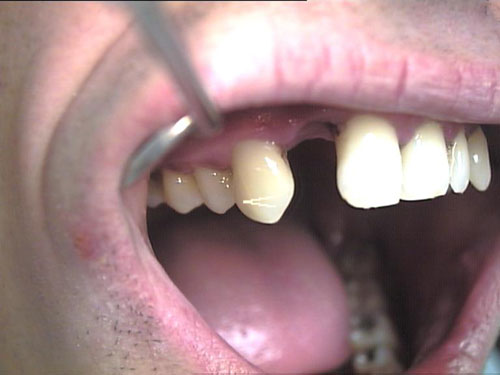

Zahnimplantate 2